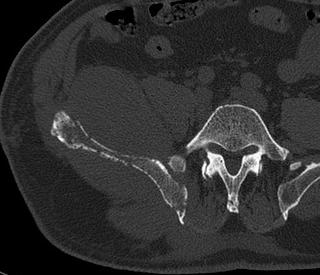

Intense homogeneous contrast enhancement

DWI Hyperintense

Periventricular lesions

Hyperdense lesion on nonconstast CT

Corpus callosum involvement